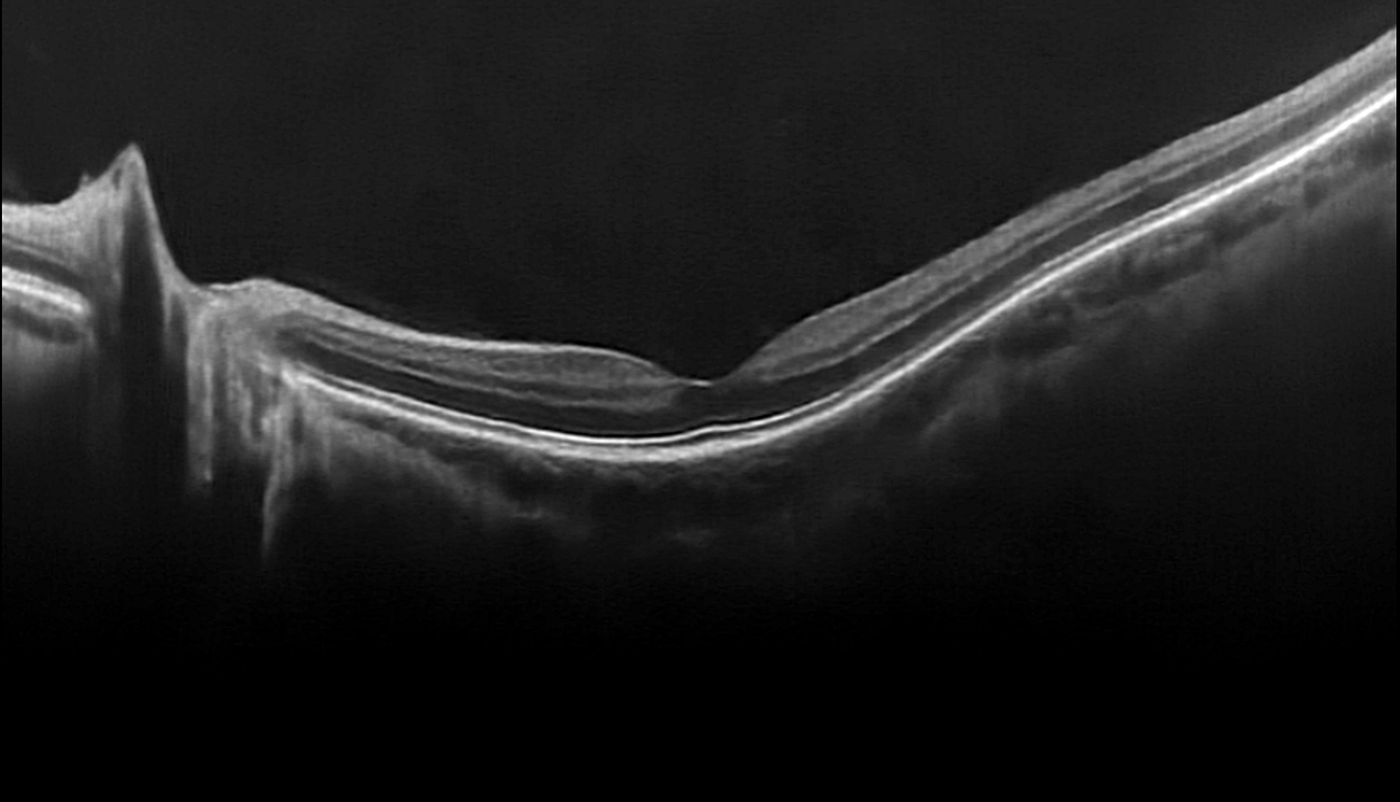

Die Optical Coherence Technology (OCT) verwendet Lichtwellen, um Querschnittsbilder Ihrer Netzhaut zu erstellen. Mit OCT können Sie jede der unterschiedlichen Schichten der Netzhaut sehen. So können Sie ihre Dicke kartieren und messen, was bei der Diagnose hilft und Behandlungsempfehlungen für Netzhauterkrankungen wie beispielsweise Glaukom, diabetische Augenkrankheiten und AMD liefert. Diese Messungen helfen bei der Diagnose.